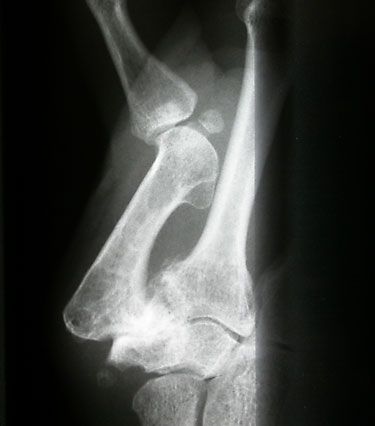

Wegweisend in der Diagnosestellung sind die geschilderten Beschwerden sowie der Untersuchungsbefund der betroffenen Gelenke mit Schwellung, Druck- und Bewegungsschmerz sowie Bewegungseinschränkung. Die Röntgenaufnahme des Gelenks in zwei Ebenen weist eine Verschmälerung des Gelenkspaltes (Knorpelverlust), Rand-Anbauten und gelenknahe Zysten nach und sichert die klare Diagnose von Arthrose.

Röntgenbild einer schwersten Daumensattelgelenkarthrose